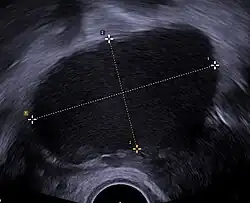

![]() Ecografía ginecológica en la que es visible un endometrioma ovárico de 67 x 40 mm. | ||

En medicina, se denomina endometrioma a un tipo de quiste que se forma en los ovarios como consecuencia de la enfermedad ginecológica llamada endometriosis. Se llama endometrioma ovárico por presentarse sobre todo en el ovario, aunque puede aparecer en otras localizaciones. Se designa también como quiste de chocolate por contener en su interior una sustancia oscura y espesa que por su aspecto puede recordar al chocolate.[1][2]Generalmente son bilaterales, es decir afectan tanto al ovario derecho como al izquierdo.